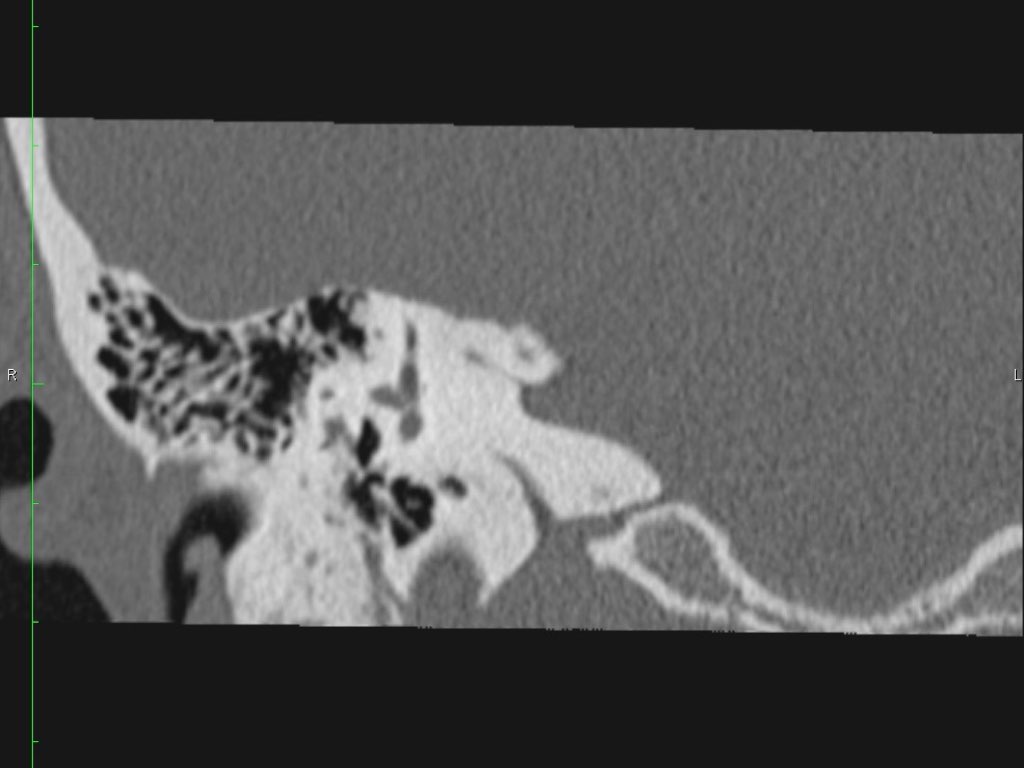

Hình ảnh một bệnh nhân có cholesteatoma.

Có một khối mô mềm ở vùng thượng nhĩ.

Lưu ý hình ảnh thủng màng nhĩ (mũi tên vàng) và bào mòn ống bán khuyên ngoài (mũi tên đỏ).

Scutum bị tù mòn.